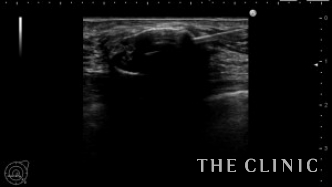

この方は被膜の厚いオイルシストがいくつかありましたが、エコーガイド下に注射針で穿刺吸引しました。

穿刺しました。ほとんど虚脱しましたが、厚い被膜がはっきり見えます。